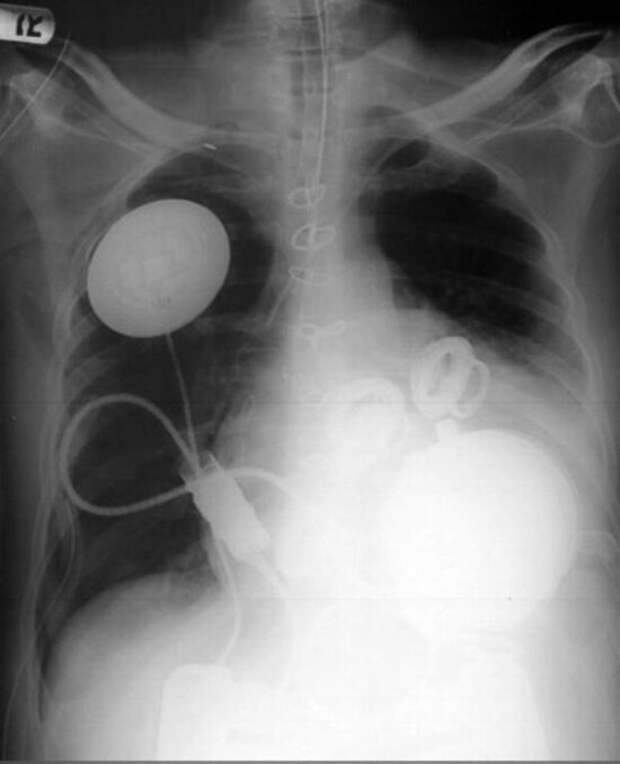

Нервные тракты, которые соединяют различные области мозга  Рентген грудной клетки с аппаратом искусственного сердца

Рентген грудной клетки с аппаратом искусственного сердца  Мозг человека в коме и мозг здорового человека